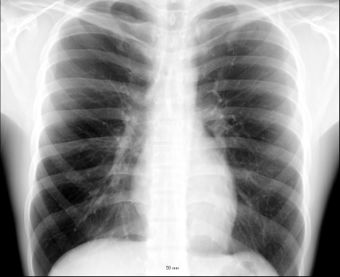

![]() تشريح الصدر | |